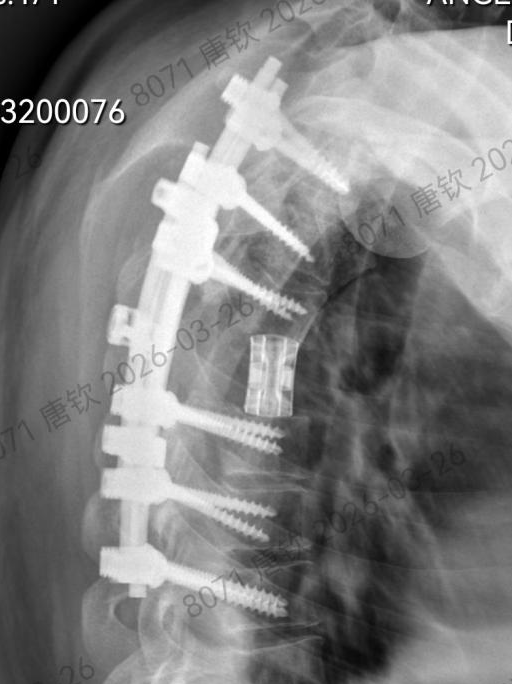

手术过程中,在脊柱外科团队戴楠主任医师、周远哲主治医师、喻博住院医师的紧密辅助配合下,唐钦主任医师沉着执刀、精准操作,在毫米级空间内精细操作、步步为营。术者凭借深厚的技术功底与极强的心理素质,完整剥离并整块取出肿瘤及受累椎体;面对脊柱稳定性重建这又一难题,团队采用目前国内最先进的3D打印人工椎体精准植入填充,配合椎弓根钉系统牢固固定,完美重建脊柱力学结构,全程实现脊髓零牵拉、零损伤,创下极限操作下的手术奇迹。

术后复查影像检查图像